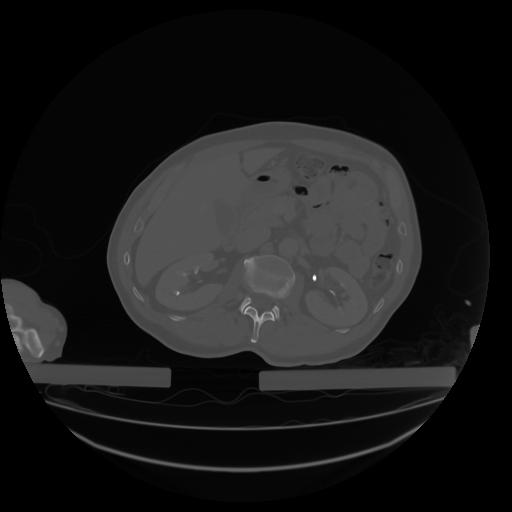

27 CUERPO,CE,Axial,3.0,CUERPO,,